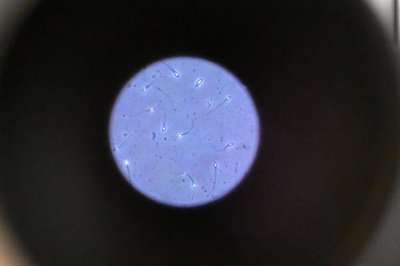

「子どもは550人」 精子スーパードナー、ネットフリックスを提訴